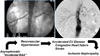

Purpose of review: Atherosclerotic renovascular disease remains highly prevalent and presents an array of clinical syndromes. Recent prospective trials have dampened enthusiasm for revascularization generally, but clinicians recognize the need to identify patients likely to benefit from vascular intervention.

Recent findings: This article highlights the inflammatory nature of vascular occlusive disease and the limits of the kidney to adapt to reduced blood flow. Although moderate reductions can be tolerated, severe impairment of renal perfusion leads to tissue hypoxia and activates inflammatory injury within the kidney. Hence, assessment of kidney viability and potential tools to modify mitochondrial and inflammatory damage may be important to identify patients for whom clinical intervention should be undertaken.